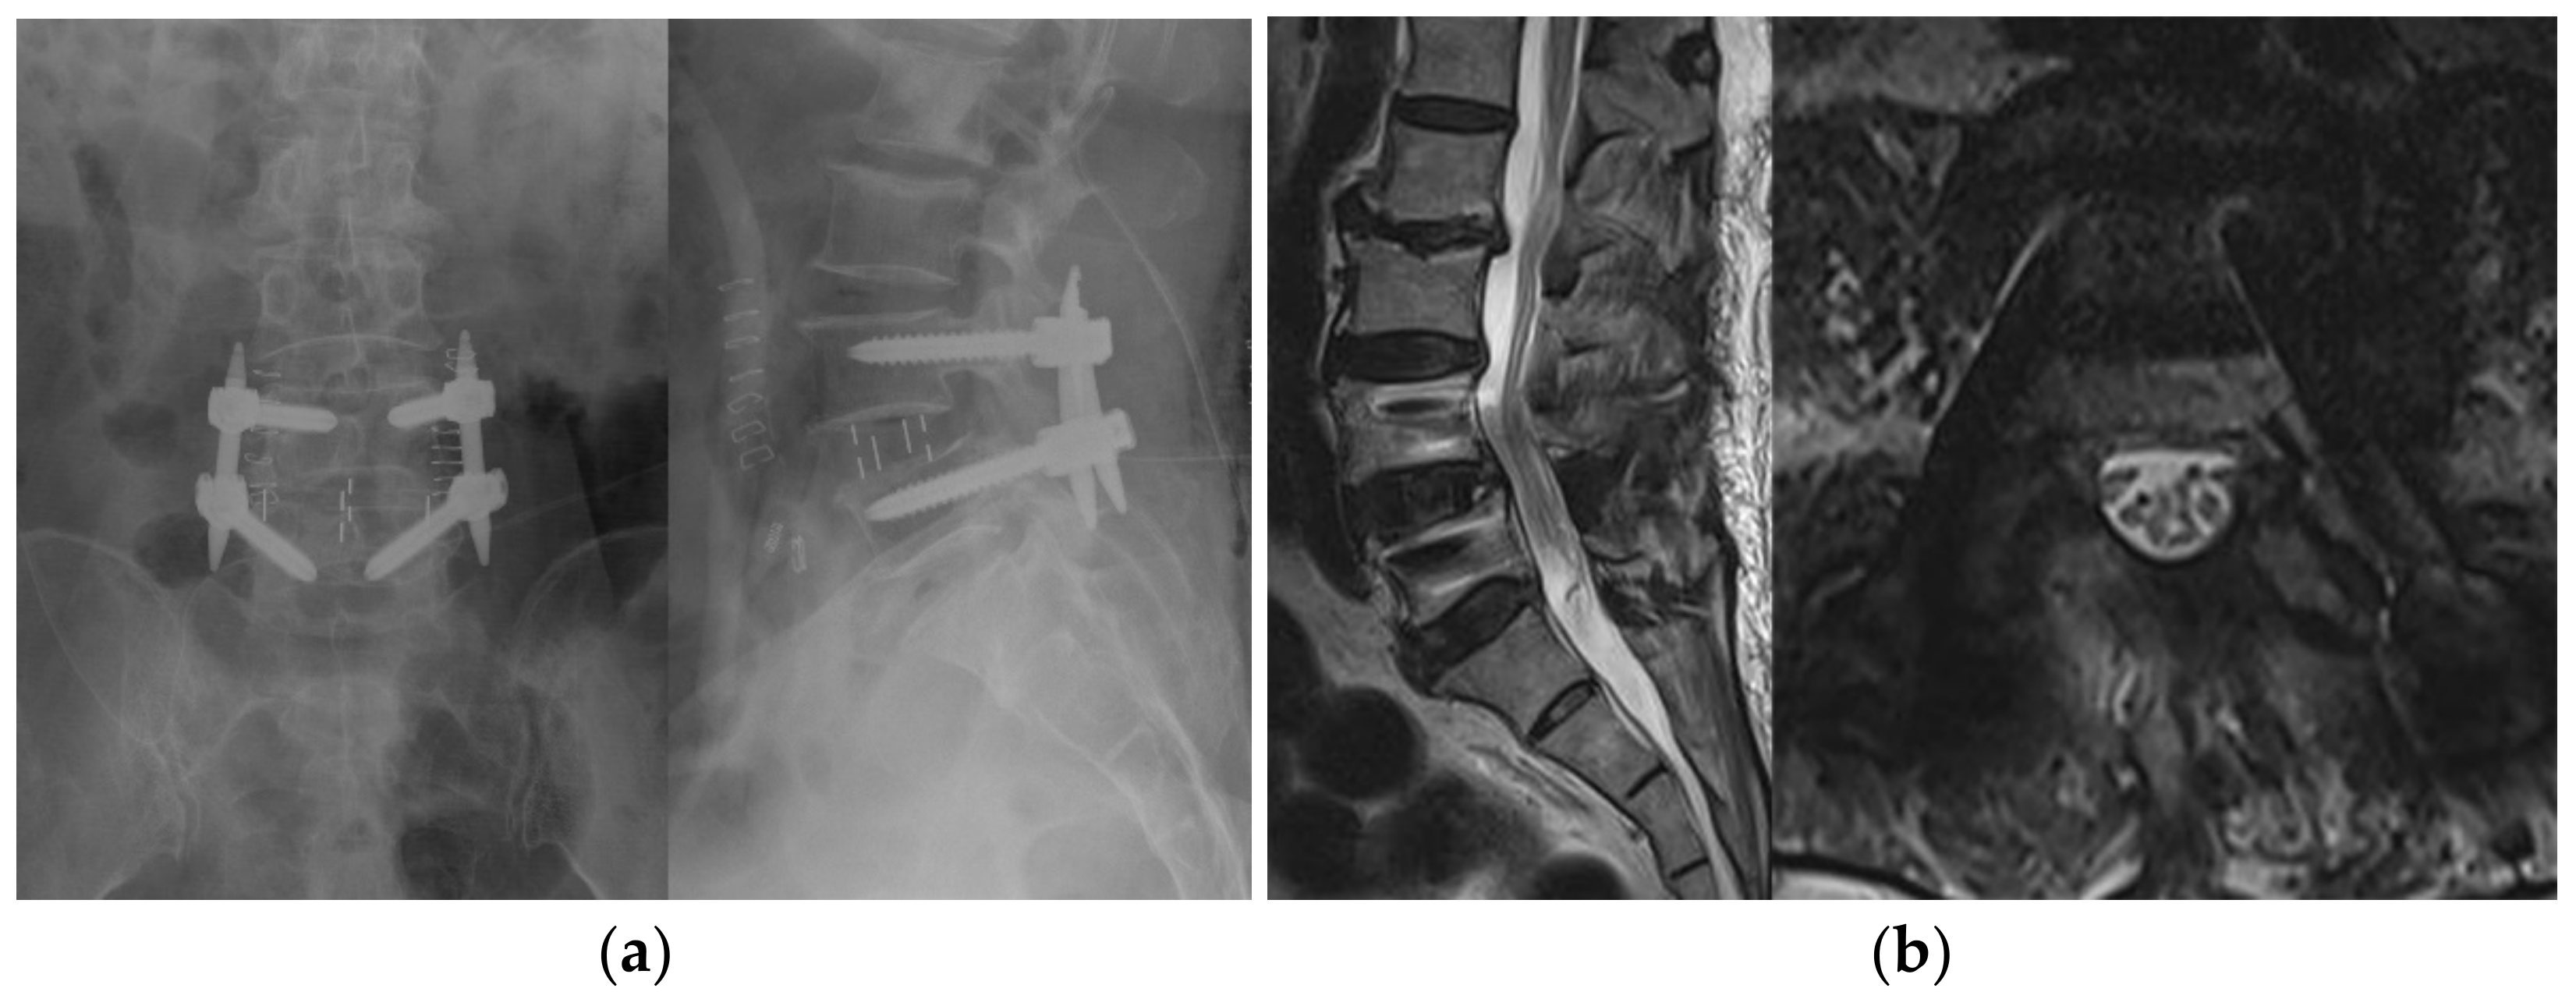

2.2.1. BESS with OLIF

2.2.2. Conventional Open TLIF